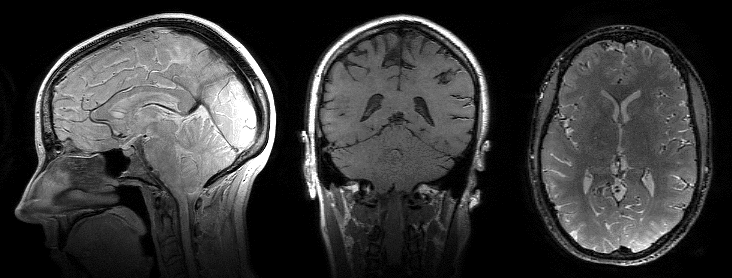

Reconstructed spin-echo image animations at different contrasts and orientations. Left: sagittal reformat at a TR of 7000 ms and TE increasing from 5 ms to 200 ms shows the T2 relaxation curve. Middle: coronal reformat at TE = 10 ms and TR increasing from 200 ms to 7000 ms shows the T1 saturation recovery curve. Right: Axial reformat at TE = 10 ms, TR = 7000 ms, and TI increasing from 50 ms to 7000 ms shows the T1 inversion recovery curve.